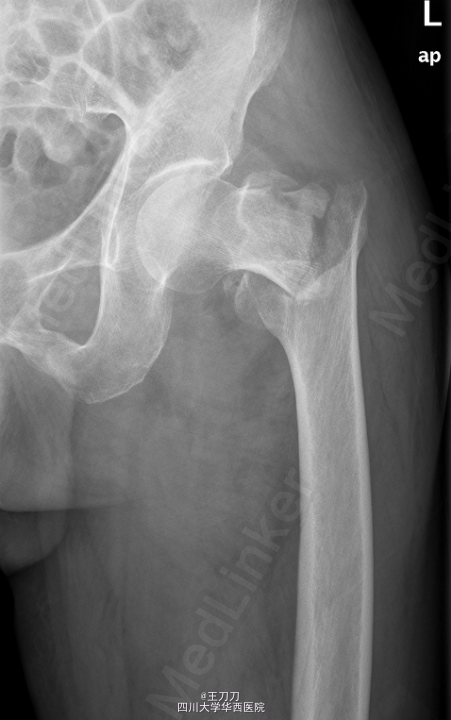

患者,男,78岁,因“摔伤致左侧髋部疼痛11天”入院。

左髋部肿胀,压痛阳性,左髋部活动受限,左下肢屈曲缩短畸形,左足趾活动可,末梢血运良好。肢体肌力查体不配合。病理征阴性。外院检查:骨盆CT示“左侧股骨粗隆间粉碎性骨折”.

初步诊断:左侧股骨颈骨折. 在全麻下行“左股骨粗隆间骨折闭合复位内固定术”. 取以左股骨大转子顶点向近端延伸切口长约5cm,逐层切开皮肤,皮下组织,纵行分离臀大肌,臀中肌纤维,触及大转子顶点,以大转子顶点前中1/3为进针点,开口,C臂机引导下置入导针至骨折断端以远。扩髓至远侧骨折端,C臂机引导下沿导针进髓内钉至合适深度,连接锁钉支架,套筒定位后切开皮肤约2cm,C臂机引导下以合适前倾角进导针经股骨颈至股骨头前端,C臂机透视见主钉位置良好,打入防旋钉后拧入主钉,拔除导针。以适宜锁定钉行远端孔锁定,取下支架。冲洗,止血,逐层缝合至皮肤,无菌敷料覆盖。